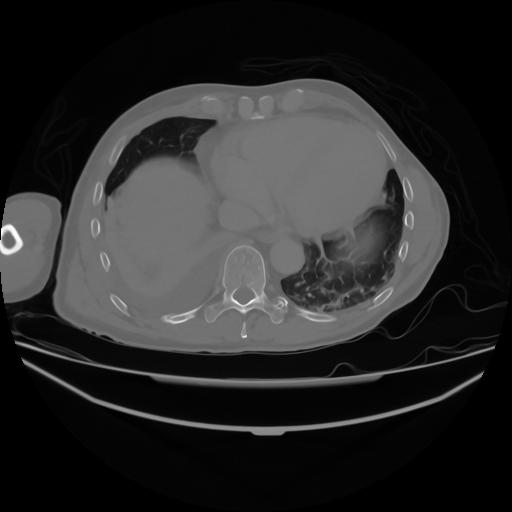

4 CUERPO,CE,Axial,3.0,CUERPO,,